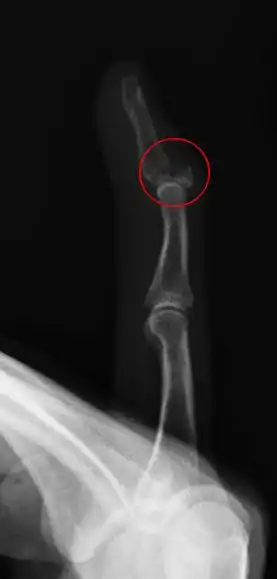

| Fracture of the dorsal base of the distal falange by extensor tendon avulsion (Busch fracture) | |

In medicine a Busch fracture[1] is a type of fracture of the base of the distal phalanx of the fingers, produced by the removal of the bone insertion (avulsion) of the extensor tendon. Without the apropiate treatment, the finger becomes a hammer finger. It would correspond to the group B of the Albertoni classification.[2] It is very common in motorcycle riders and soccer joggers, caused by a hyperflection when the tendon is exercising the maximum tension (the closed hand tightening the clutch lever or the brake lever ).[3][4]

The mechanism of this injury can be described as an avulsion of the tendon fixed to the distal falange.[6][7][8]